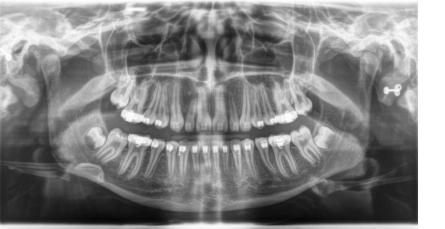

sehr hohe Auflösung und Kontrast sehr geringe Strahlenbelastung sofortige Bilddarstellung in Echtzeit optimale Vergrößerungsmöglichkeiten umfangreiche Bildnachbearbeitung punktgenaue Vermessung von Strecken gemeinsame Ergebnisauswertung mit dem Patienten Hochauflösende Panoramaaufnahme: